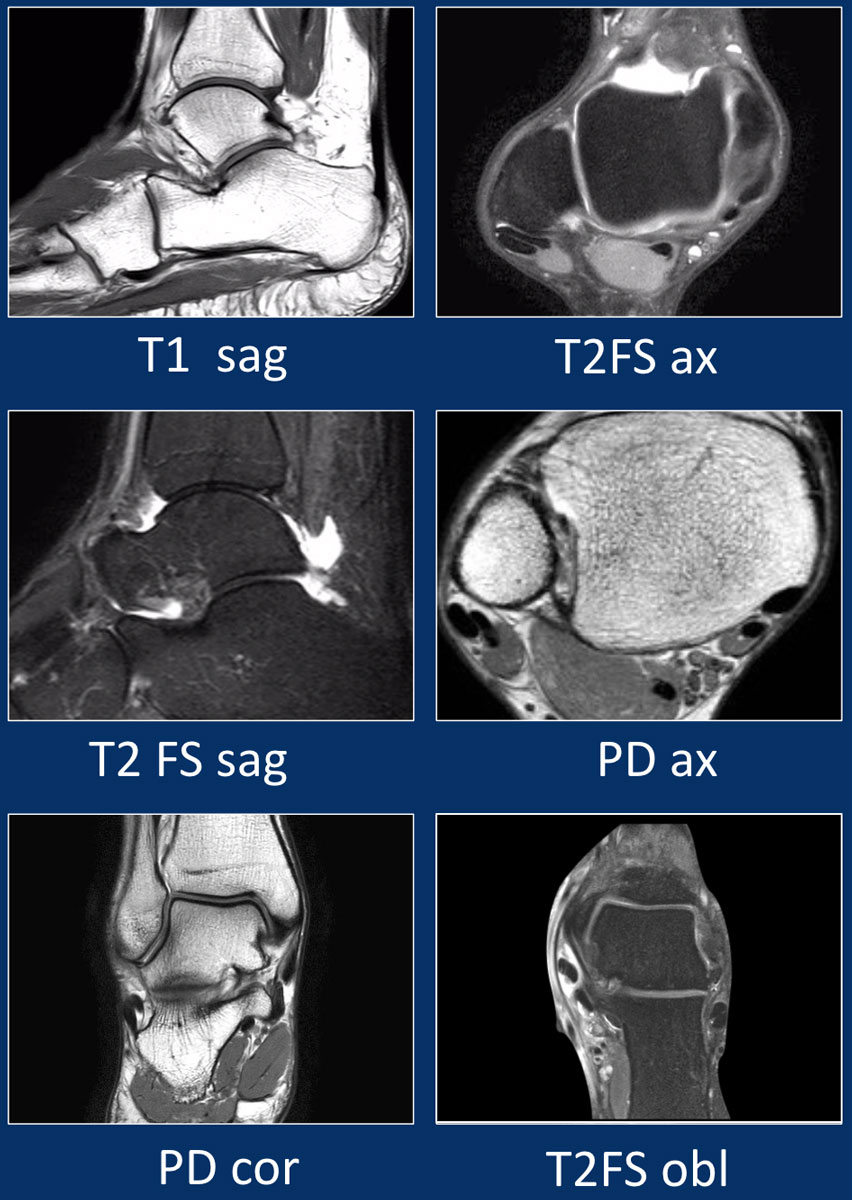

From radiologyassistant.nl

The Radiology Assistant Ankle MRI examination What Is A Mri Protocol Mri allows the acquisition of images with excellent tissue contrast and. Mri protocols are a combination of various mri sequences, designed to optimally assess a particular region of the body and/or pathological. When you put a patient in a strong. Mri machines work by exploiting the interaction of the magnetic field, hydrogen ions, and radiofrequency (rf) pulse. Mri is one. What Is A Mri Protocol.